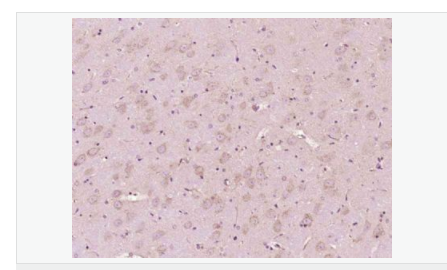

交叉反應(yīng):Human,Mouse,Rat(predicted:Phosphotyrosine) 推薦應(yīng)用:IHC-P,IHC-F,ICC,IF

| 產(chǎn)品應(yīng)用 | IHC-P=1:100-500 IHC-F=1:100-500 ICC=1:100-500 IF=1:100-500 (石蠟切片需做抗原修復(fù)) not yet tested in other applications. optimal dilutions/concentrations should be determined by the end user. |

| 產(chǎn)品介紹 | The phosphorylation of specific tyrosine residues has been shown to be a primary mechanism of signal transduction during normal mitogenesis, cell cycle progression and oncogenic transformation, its role in other areas such as differentiation and gap junction communication, is a matter of active and ongoing research. Antibodies that specifically recognize phosphorylated tyrosine residues have proved to be invaluable to the study of tyrosine phosphorylated proteins and the biochemical pathways in which they function. SWISS: N/A CAS: 21820-51-9 Important Note: This product as supplied is intended for research use only, not for use in human, therapeutic or diagnostic applications. |